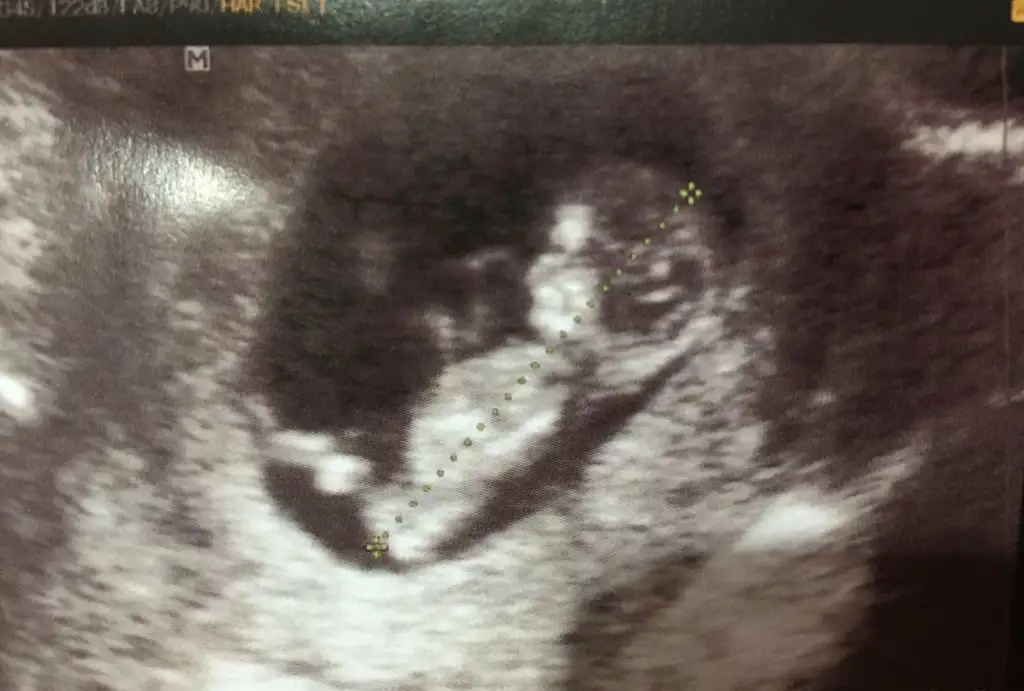

Bence kız cnmKızlar benim bebeğiminde cinsiyet tahminini yapar mısınız?

Kızlar benim bebeğiminde cinsiyet tahminini yapar mısınız?